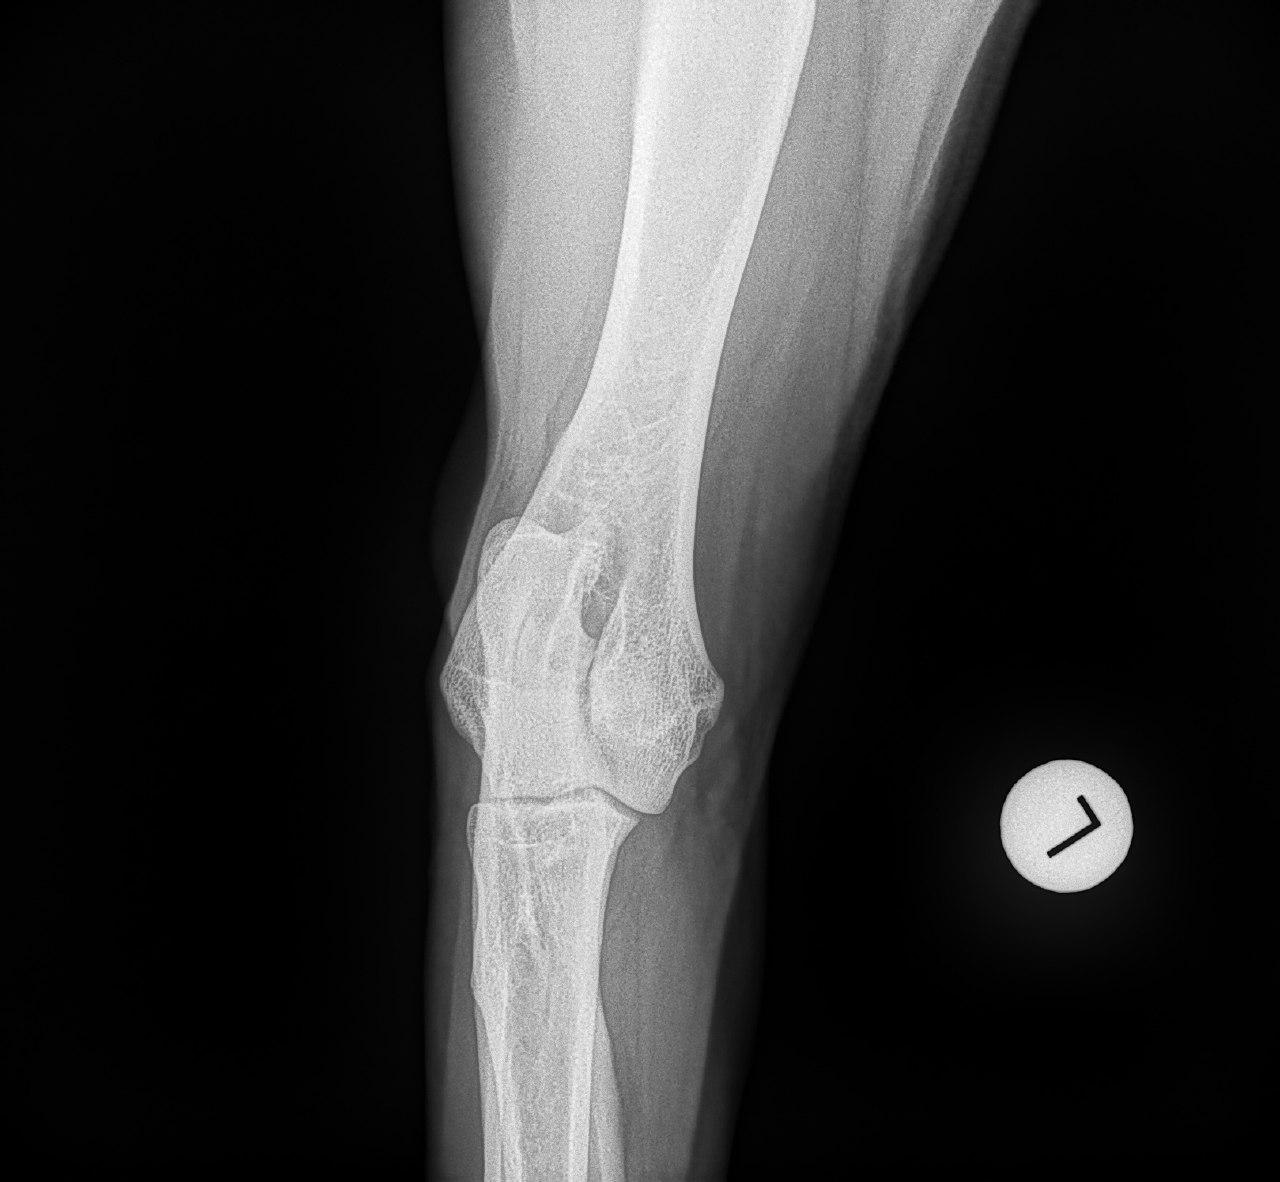

Mit der HD ist das so ne Sache..... die Vererbung spielt eine sehr große Rolle, ja. Aber bei unserer Peggy Zb ist es so, dass mehrere Generationen nachweislich HD und ED frei sind und auch frei von Spondylosen. Als einziger Hund überhaupt in der gesamten Zucht hat unsere Dame alles mitgenommen, was zu kriegen war;(: sie hat nicht nur schwere HD, weil ihre Hüfte viel zu locker ist, sondern dadurch bedingt am rechten Knie bereits schwere Arthrose und hinten links eine Sehenschwäche (durch Überlastung), weshalb sie dort durchtrittig ist. Und als würde das alles nicht schon vollkommen reichen, wurden aktuell auch noch mehrere heftige Spondylosen diagnostiziert;(. An einer Stelle ist sogar schon etwas abgebrochen8|.